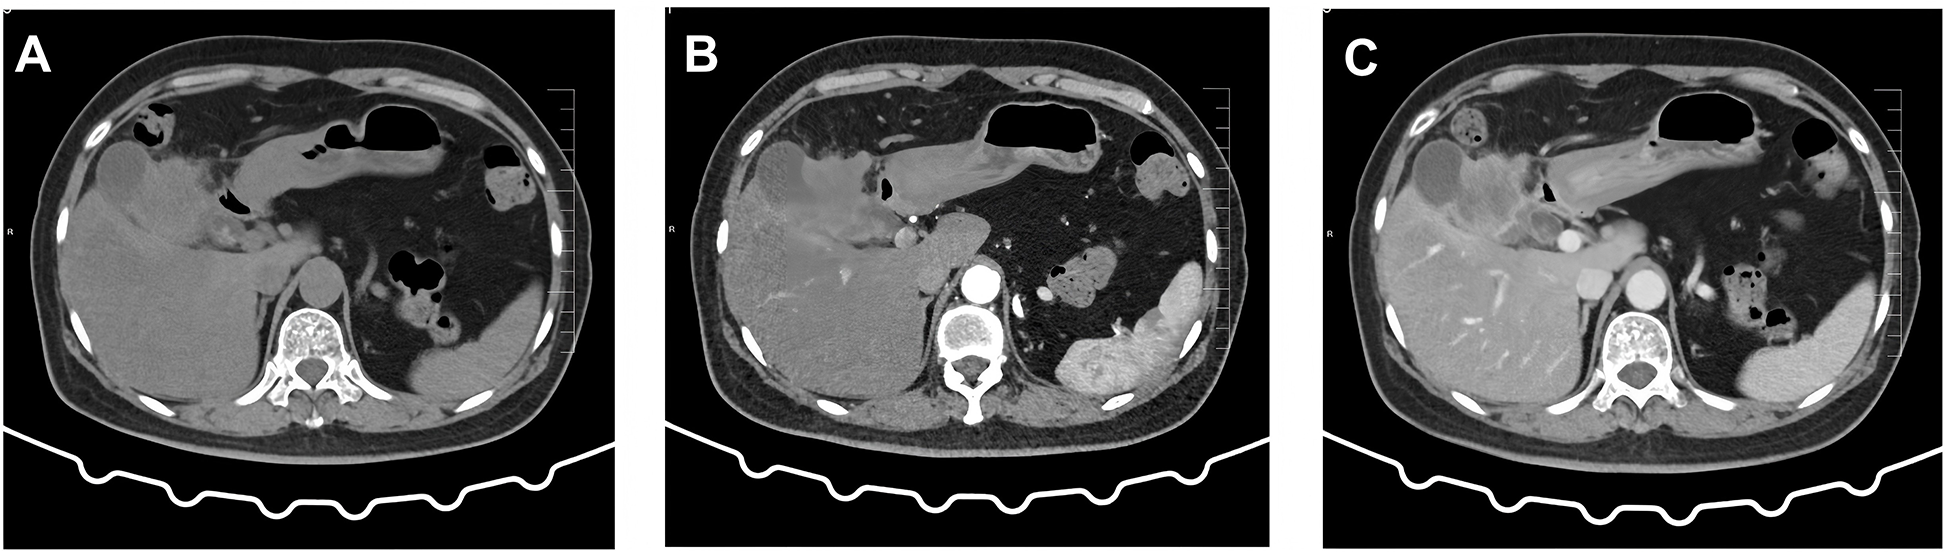

A 60-year-old female patient was admitted to the hospital on December 06, 2023, due to “upper abdominal pain for 20 days”. She was previously in good health. Physical examination revealed epigastric tenderness with rebound tenderness, and Murphy’s sign was positive. Laboratory examination showed that carbohydrate antigen 19-9 (CA19-9), carbohydrate antigen 125 (CA125), carcinoembryonic antigen (CEA), alpha-fetoprotein (AFP), etc., were normal. Preoperative abdominal CT scan and enhancement are shown in Figure 1. Preoperative abdominal CT with plain and contrast-enhanced scans (Figure 1) revealed an irregular mass lesion measuring approximately 3.8 × 3.0 cm at the gallbladder site. On plain scan, it appeared slightly hypodense with ill-defined margins. During the arterial phase of contrast enhancement, it demonstrated heterogeneous, marked enhancement. In the venous phase, enhancement persisted but showed slight attenuation. It was accompanied by irregular thickening of the gallbladder wall and infiltrative growth into adjacent hepatic parenchyma (segments IVb and V). Mild dilatation of intrahepatic bile ducts was noted. Imaging features suggested a highly malignant gallbladder tumor, consistent with gallbladder carcinoma, with possible local liver involvement. Main diagnosis was as follows: 1) gallbladder space-occupying: gallbladder cancer? On December 10, 2023, the patient underwent a radical laparoscopic cholecystectomy for gallbladder cancer. The procedure included radical cholecystectomy for gallbladder cancer + segmental resection of segments IVb and V of the liver + lymph node dissection of the hepatoduodenal ligament + exploration of the common bile duct + T-tube drainage. The gallbladder fundus exhibited a grayish-white cut surface with a firm, hard texture. The lesion measured approximately 3.0 × 3.3 cm. Twelve lymph nodes were resected and submitted for examination during the procedure. Pathological examination showed the following: (gallbladder + liver segments 4, 5, 6 + hilar lymph nodes) gallbladder-mixed adenoneuroendocrine carcinomas, of which neuroendocrine carcinomas accounted for approximately 70%, exocrine carcinomas accounted for approximately 30%, and exocrine carcinomas accounted for approximately 30%. Approximately 15% of the carcinomas were moderately differentiated tubular adenocarcinomas, and 15% were moderately differentiated squamous cell carcinomas, which invaded the whole thickness of the gallbladder wall and invaded the serosal surface. Nerve invasion, multifocal hemorrhage, necrosis, and lymph nodes (0/12) were observed. Immunohistochemical results were as follows: NEC components Ki-67 (+80%), p63 (−), CK5/6 (+), CK7 (−), CK20 (+), Villin (−), CDX2 (−), mutation synaptophysin (Syn) (+), neuron-specific enolase (NSE) (−), CD56 (+), CK (pan) (−), and CD34 blood vessel (+), as shown in Figure 2. Final pathological staging (American Joint Committee on Cancer (AJCC) 8th edition) was pT3N0M0, Stage III A. The tumor invaded the entire wall of the gallbladder and penetrated the serosa, extending into adjacent liver parenchyma (segments IVb and V), but the resection margins were negative (R0 resection). All 12 lymph nodes in the hepatoduodenal ligament were free of metastasis (0/12). There was no evidence of distant metastasis on intraoperative examination or imaging studies. The patient received six cycles of etoposide plus cisplatin (EP) adjuvant chemotherapy (January–May 2024). Follow-up protocol included clinical evaluation (physical exam and symptom assessment) every 3 months, laboratory tests (Complete Blood Count (CBC), liver/kidney function, CA19-9, CEA, and NSE), and imaging (contrast-enhanced abdominal/pelvic CT + chest CT). As of December 2024 (12 months after operation), four follow-ups were completed with no evidence of recurrence or metastasis. Current disease-free survival (DFS) was 12 months with good performance status.

Figure 1

Preoperative abdominal CT findings. (A) Conventional scan reveals a low-density mass with indistinct borders in the gallbladder region. (B) Arterial phase scan shows heterogeneous enhancement in the surrounding area. (C) Venous phase scan demonstrates persistent but slightly diminished enhancement. The mass invades adjacent hepatic parenchyma (segments IVb and V), suggesting a localized gallbladder malignancy.